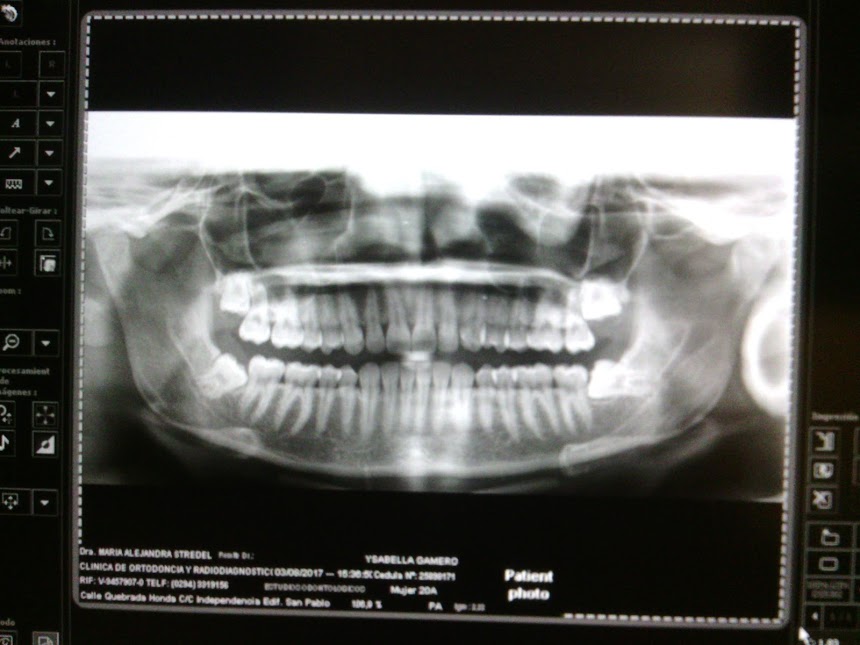

Aqui les mostrare la panoramica de mi boca y lo dificil que estaban de extraer .

Here I will show you the panoramas of my mouth and how difficult they were to extract.

Panoramica